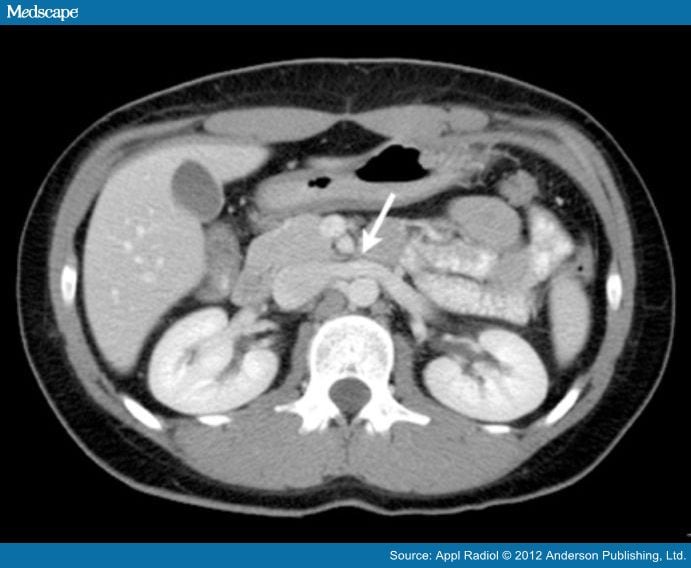

Axial CT section demonstrating the anatomy of Nutcracker phenomenon and Nutcracker Syndrome Anatomy Nutcracker syndrome (ncs) describes left renal vein compression between the superior mesenteric artery and the aorta. The most common clinical manifestations of nutcracker syndrome are left flank pain, pelvic pain,. Nutcracker syndrome (ncs) is an extrinsic compression of the left renal vein (lrv) by the superior mesenteric artery (sma). The nutcracker syndrome is a rare and often unrecognized cause of. Nutcracker Syndrome Anatomy.